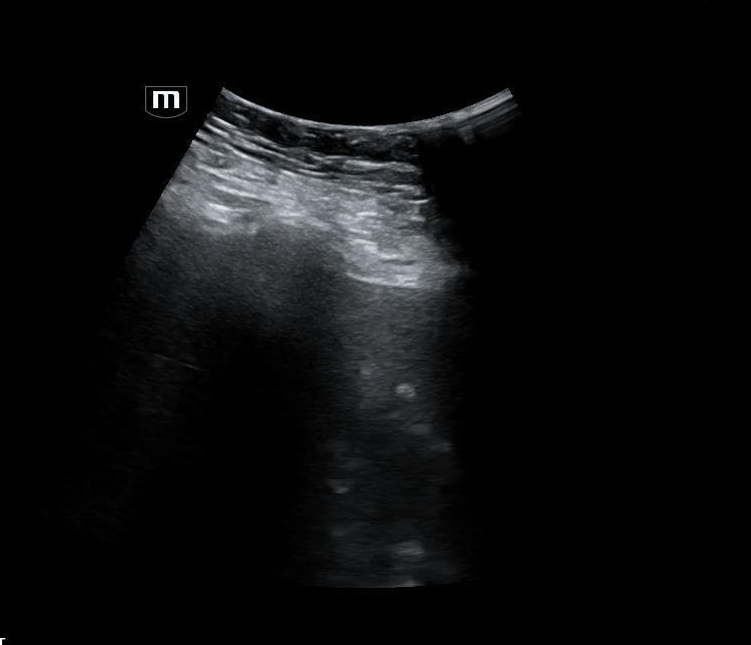

Torsion

Booth EMOctober 15, 2025

What's in that scrotum?

Booth EMJuly 23, 2025